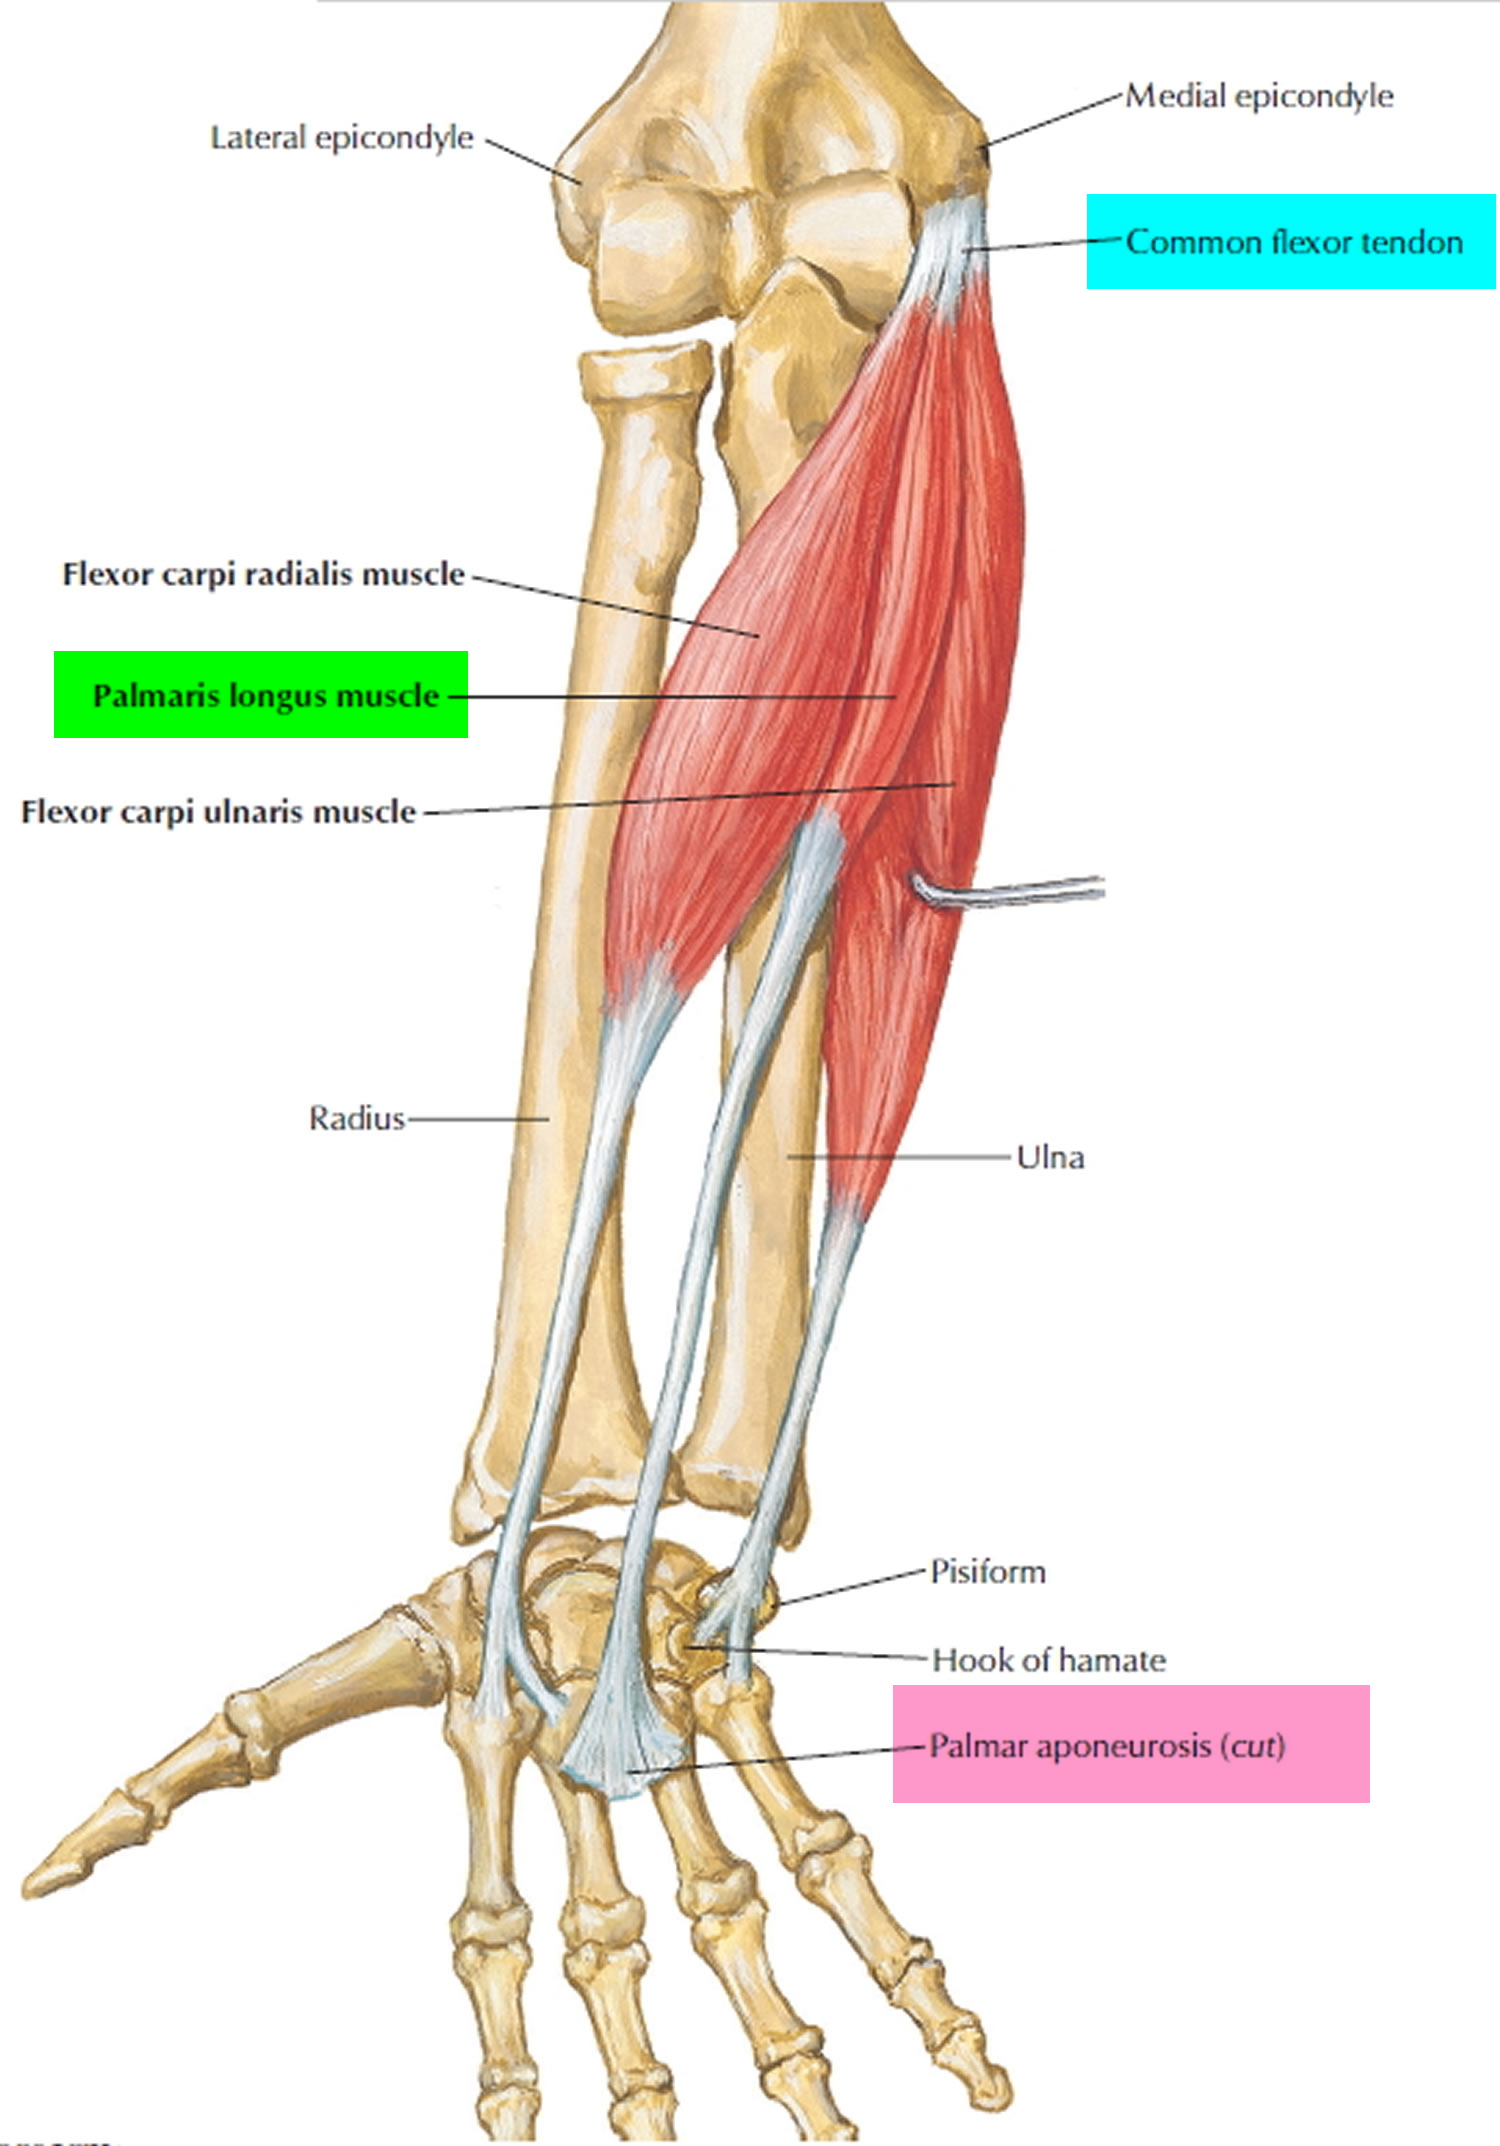

Анатомия мышцы Palmaris Longus